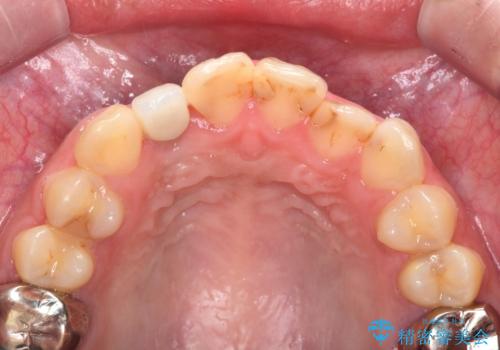

- 虫歯の治療を繰り返した前歯の見た目の改善を求めて来院されました。

大きく詰められたコンポジットレジンと虫歯の再発が見られ、経年劣化により審美性も損なわれていました。

充填されたコンポジットレジン・再発した虫歯を神経に影響が出ないよう丁寧に除去し再充填をしたのちオールセラミッククラウンで前歯の審美性を回復します。